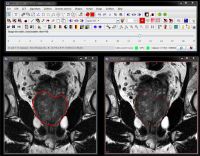

Sagittal and coronal images. Repeat the same process of delineating and smoothing VOIs for both sagittal and coronal images. In the sample image dataset provided, the saggital image name is img_sag_83 and the coronal image name is img_cor_83. See Naming Conventions.

In the sample image dataset provided, VOIs files are already available for all 3 types of images (axial, saggital and coronal). Under the image dataset directory, one can find 3 orthogonal images and corresponding VOIs:

| coronal | img_cor_83.xml | voi_cor_83.xml |

| saggital | img_sag_83.xml | voi_sag_83.xml |